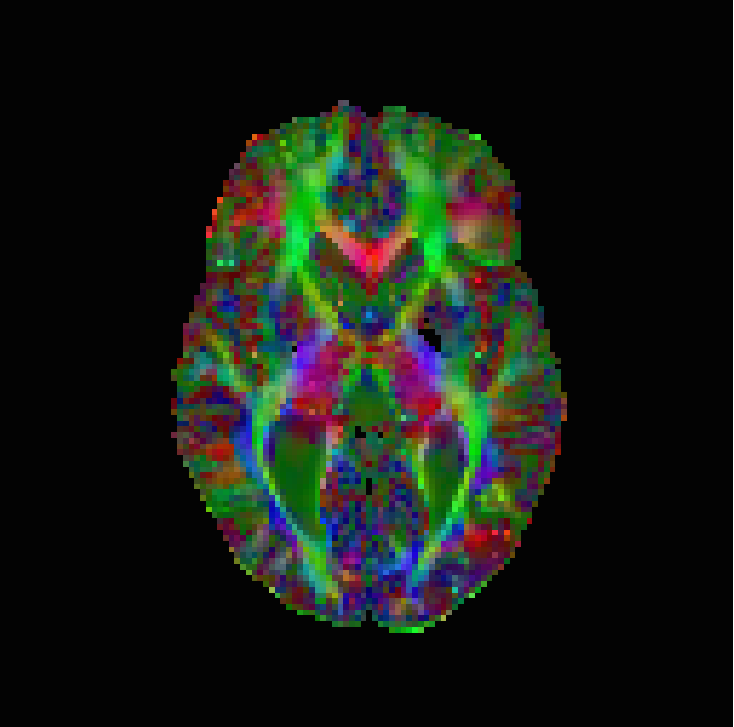

The numerical results are in Table 1 and Figures 3–5, with the first of the figures showing the colour-coded principal eigenvector of the reconstruction, the second showing the fractional anisotropy and principal eigenvectors, and the last one the errors in the latter two, in a colour-coded manner. All plots are masked to represent only the non-zero region. The field of fractional anisotropy is defined for a field of 2-tensors on as

As we can see, the non-linear approach (3.2) performs overall the best by a wide margin, in terms of the pointwise Frobenius error, i.e., error in . This is expressed as a PSNR in Table 1. What is, however, interesting, is that the constraint-based approach (3.5) has a much better reconstruction of the principal eigenvector angle, and a comparable reconstruction of its magnitude. Indeed, the 95% confidence interval in Figure 3(g) and Figure 4(g) suggests a nearly perfect reconstruction in terms of smoothness. But, the Frobenius PSNR in Table 1 for this approach is worse than the simple unregularised inversion by regression. The problem is revealed by Figure 5(f): the large white cloudy areas indicate huge fractional anisotropy errors, while at the same time, the principal eigenvector angle errors expressed in colour are much lower than for other approaches. Good reconstruction of the principal eigenvector is important for the process of tractography, i.e., the reconstruction of neural pathways in a brain. One explanation for our good results is that the regulariser completely governs the solution in areas where the error bounds are inactive due to generally low errors. This results in very smooth reconstructions, which is in the present case desirable as our synthetic tensor field is also smooth within the helix.

The results are in Table 2 and Figures 6–8, again with the first of the figures showing the colour-coded principal eigenvector of the reconstruction, the second showing the fractional anisotropy and principal eigenvectors, and the last one the errors in the latter two, in a colour-coded manner. Again, all plots are masked to represent only the non-zero region. In the figures, we concentrate on error bounds based on 95% confidence intervals, as the results for the 90% and 99% cases do not differ significantly according to Table 2.